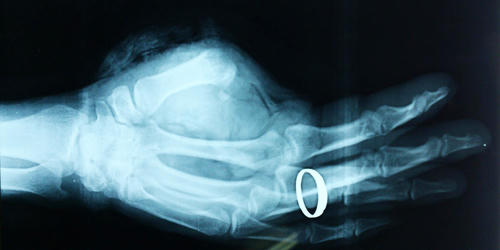

Trước đó, bệnh nhân Lê Văn Cường (SN 1980, trú tại huyện Nghi Lộc, Nghệ An) được người nhà chuyển tới Bệnh viện Chấn thương chỉnh hình Nghệ An trong tình trạng đứt lìa ngón cái tay trái, mất nhiều máu, vết đứt sắc ngọt… Người nhà còn mang theo phần ngón cái bị đứt rời đã được bảo quản lạnh và đưa tới bệnh viện. Qua thăm khám, hội chẩn khẩn cấp và quyết định phẫu thuật nối ngón tay ngay.

Ca mổ diễn ra liên tục trong vòng 8 tiếng đồng hồ, để nối các mạch máu và xương của ngón tay với nhiều bác sỹ, y tá cùng với hệ thống thiết bị hiện đại như kính hiển vi, bộ dụng cụ vi phẫu, chỉ vi phẫu... Sau gần một tuần ca phẫu thuật tiến hành thành công ngón tay của anh Cường đã bắt đầu cử động được và tiến triển tốt lên dần, vết nối cũng liền mạch đẹp. Vết thương có xuất hiện một số biểu hiện ứ máu nhưng được bác sĩ dùng thuốc chống đông máu và giãn mạch nên hồi phục tốt.